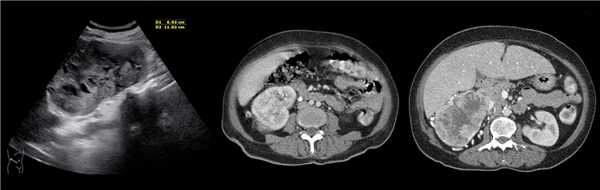

В марте 2002 г. в связи с эпизодом лейкоцитурии лечился у нефролога; при контрольном УЗИ впервые диагностированы изменения в мочевом пузыре и паравезикально слева. При повторном УЗИ выявлено (рис. 1а): правая почка увеличена в размерах (длина 12,7см; толщина паренхимы 1,6 см); чашечно-лоханочная система не расширена. Левая почка отсутствует. Стенки мочевого пузыря не изменены; в просвете слева определяется округлое образование 3,5 x 4,6 x 5,0 см с неоднородным содержимым (объем около 40 мл). Заключение: аплазия левой почки; уретероцеле слева.

а) Эхограмма.

б) Компьютерная томограмма.

в) Схема КТ.

Компьютерная томография (КТ): в проекции устья левого мочеточника и на фоне мочевого пузыря слева определяется дополнительная тень 3,1 x 4,0 x 4,0 см с четкими контурами и плотной стенкой. Мочеточник выше устья расширен до 1 см. Заключение: КТ-картина уретероцеле слева, уретерэктазия слева (рис. 1 б, в).